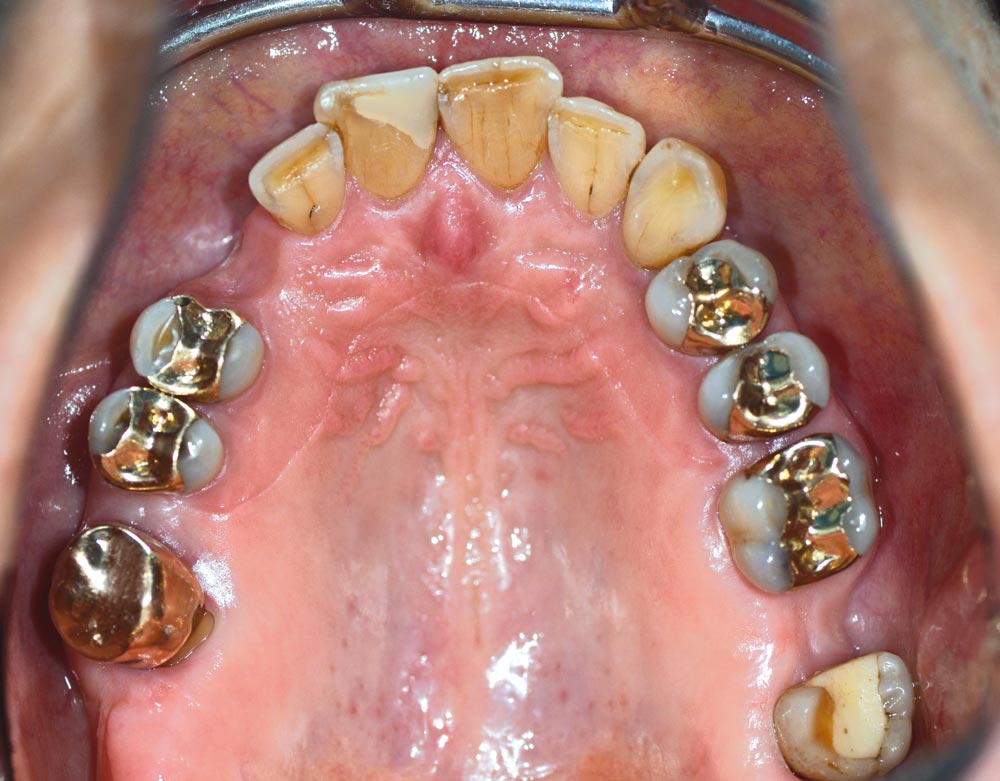

02/12 - Occlusal view of initial situation

Block augmentation with maxgraft® in the maxilla - PD Dr. Dr. F. Kloss